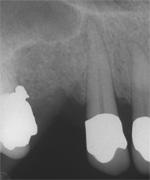

1 und 2 sind von 2000, die 3. ist vom 10.06.2010

Wurzelkanalbehandlung und Resektion wurden innerhalb eines Monats abgearbeitet und sind hier erwähnenswert auch nur vielleicht, weil von Natur aus lange Eckzahnwurzeln intra operationem subjektiv endlos lang werden können und weil hier

der Behandlungserfolg 10 Jahre nach dem Eingriff durch eine neue Aufnahme belegt werden kann. Wie alle anderen Aufnahmen auch,